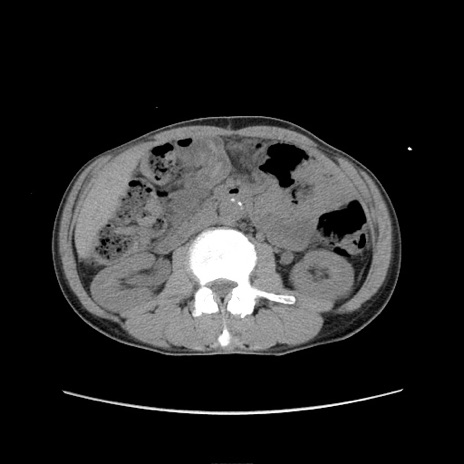

症例11(横断像)

【症例】 60歳代男性

【主訴】 下腹部痛

【現病歴】 本日夜中より下腹部痛の症状認め、受診。

【既往歴】 膀胱癌(膀胱全摘+尿管皮膚瘻術) 、胃癌術後

【身体所見】 BT 35.3℃、PR 58/min、BP 136/98mHg、腹部平坦、軟、腸蠕動音±、ストマ留置あり、左上腹部~正中部に圧痛あり、反跳痛なし。

【データ】WBC 5100、CRP0.01